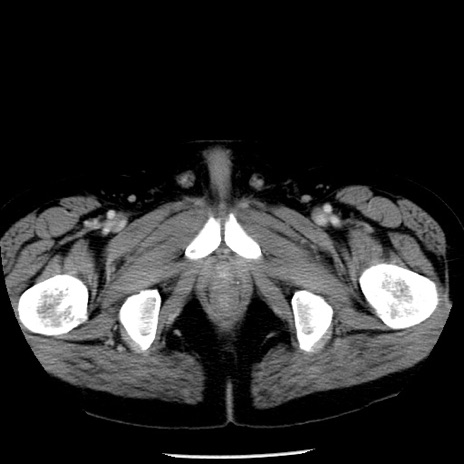

症例29(横断像)

【症例】40歳代男性

【現病歴】2日前から胃痛あり。徐々に周期的な激痛に変化した。本日になっても激痛があるため受診。

【身体所見】意識清明、BT 38-39℃台あり、腹部:膨満、やや硬、右下腹部に圧痛あり。

【データ】WBC 8500、CRP 23.26